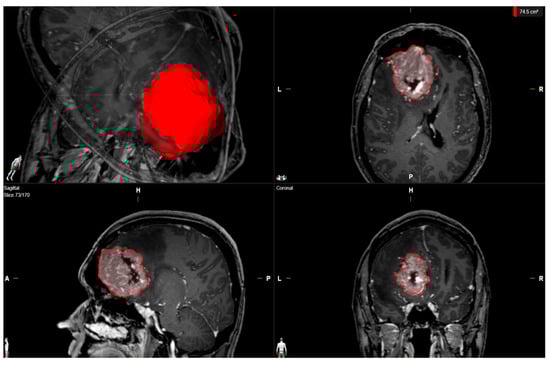

| Median baseline tumor volume (cm3, 25th–75th percentile) | 46.0 (22.4–72.4) |